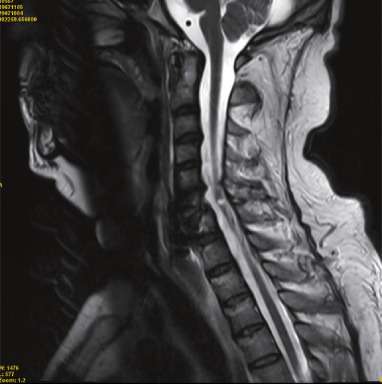

El daño a la médula espinal puede producirse debido a una variedad de mecanismos traumáticos, y aunque las lesiones por latigazo cervical pueden implicar cierta alteración de las estructuras vertebrales, es importante comprender que las lesiones graves de la médula espinal están comúnmente asociadas con fracturas y dislocaciones de las vértebras que resultan en una compresión significativa o en deformidades angulares de la médula. Este tipo de daño es más prevalente en las regiones cervical y torácica baja o lumbar superior, áreas que son especialmente vulnerables a fuerzas mecánicas traumáticas debido a la estructura y movilidad de la columna vertebral en estas zonas.

El latigazo cervical, que generalmente ocurre como consecuencia de un impacto violento y repentino, como en los accidentes de tráfico, provoca un movimiento brusco de la cabeza hacia adelante y luego hacia atrás, con una velocidad y amplitud que puede superar la capacidad de adaptación de los tejidos blandos y las estructuras de la columna vertebral. Si bien esta lesión puede afectar los músculos, ligamentos y discos intervertebrales, la médula espinal, por lo general, no se ve directamente comprometida a menos que haya una alteración significativa en la alineación o estabilidad de la columna vertebral. En casos severos, el latigazo cervical podría provocar una distorsión de las raíces nerviosas cervicales o incluso lesiones menores en la médula, pero las consecuencias graves de daño medular son más frecuentes en situaciones en las que hay fracturas o dislocaciones de las vértebras.

Las fracturas y dislocaciones vertebrales, por otro lado, son causantes más frecuentes de lesiones graves de la médula espinal, ya que estas condiciones implican un desplazamiento o ruptura de las vértebras que rodean y protegen la médula. Cuando las vértebras se fracturan o se desplazan, las estructuras óseas pueden ejercer una presión directa sobre la médula espinal, lo que provoca la compresión de las fibras nerviosas que la componen. Esta compresión puede interrumpir la transmisión de señales nerviosas entre el cerebro y el resto del cuerpo, lo que da lugar a una variedad de déficits neurológicos que dependen de la ubicación y la gravedad del daño.

Además, las dislocaciones vertebrales pueden generar deformidades angulares, donde las vértebras se desalinean de tal forma que generan un ángulo inusual que comprime la médula espinal en un área específica. Este tipo de daño puede ser particularmente devastador porque las fuerzas de compresión no solo afectan a la médula, sino también a sus conexiones con las raíces nerviosas que emergen de la columna vertebral. En las regiones cervical, torácica baja y lumbar superior, donde las vértebras son más propensas a sufrir fracturas debido a las fuerzas de impacto, el riesgo de una compresión medular severa es considerablemente mayor, lo que lleva a lesiones neurológicas graves.